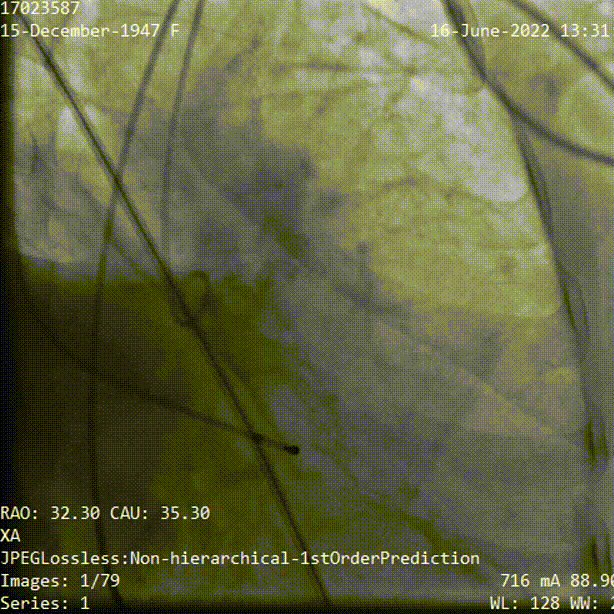

TaurusElite输送系统轻松过弓、跨瓣,AV23瓣膜瓣环上0mm定位释放,到工作位后造影显示瓣膜形态、位置良好。

瓣膜定位

释放到工作位观察

释放脱钩后瓣膜形态、位置良好,冠脉血流灌注正常,微量瓣周漏;采用22mm球囊后扩,无压差,无瓣周漏;弓部血管造影未见异常。

球囊后扩

术后根部造影

术后压差

术后经胸超声